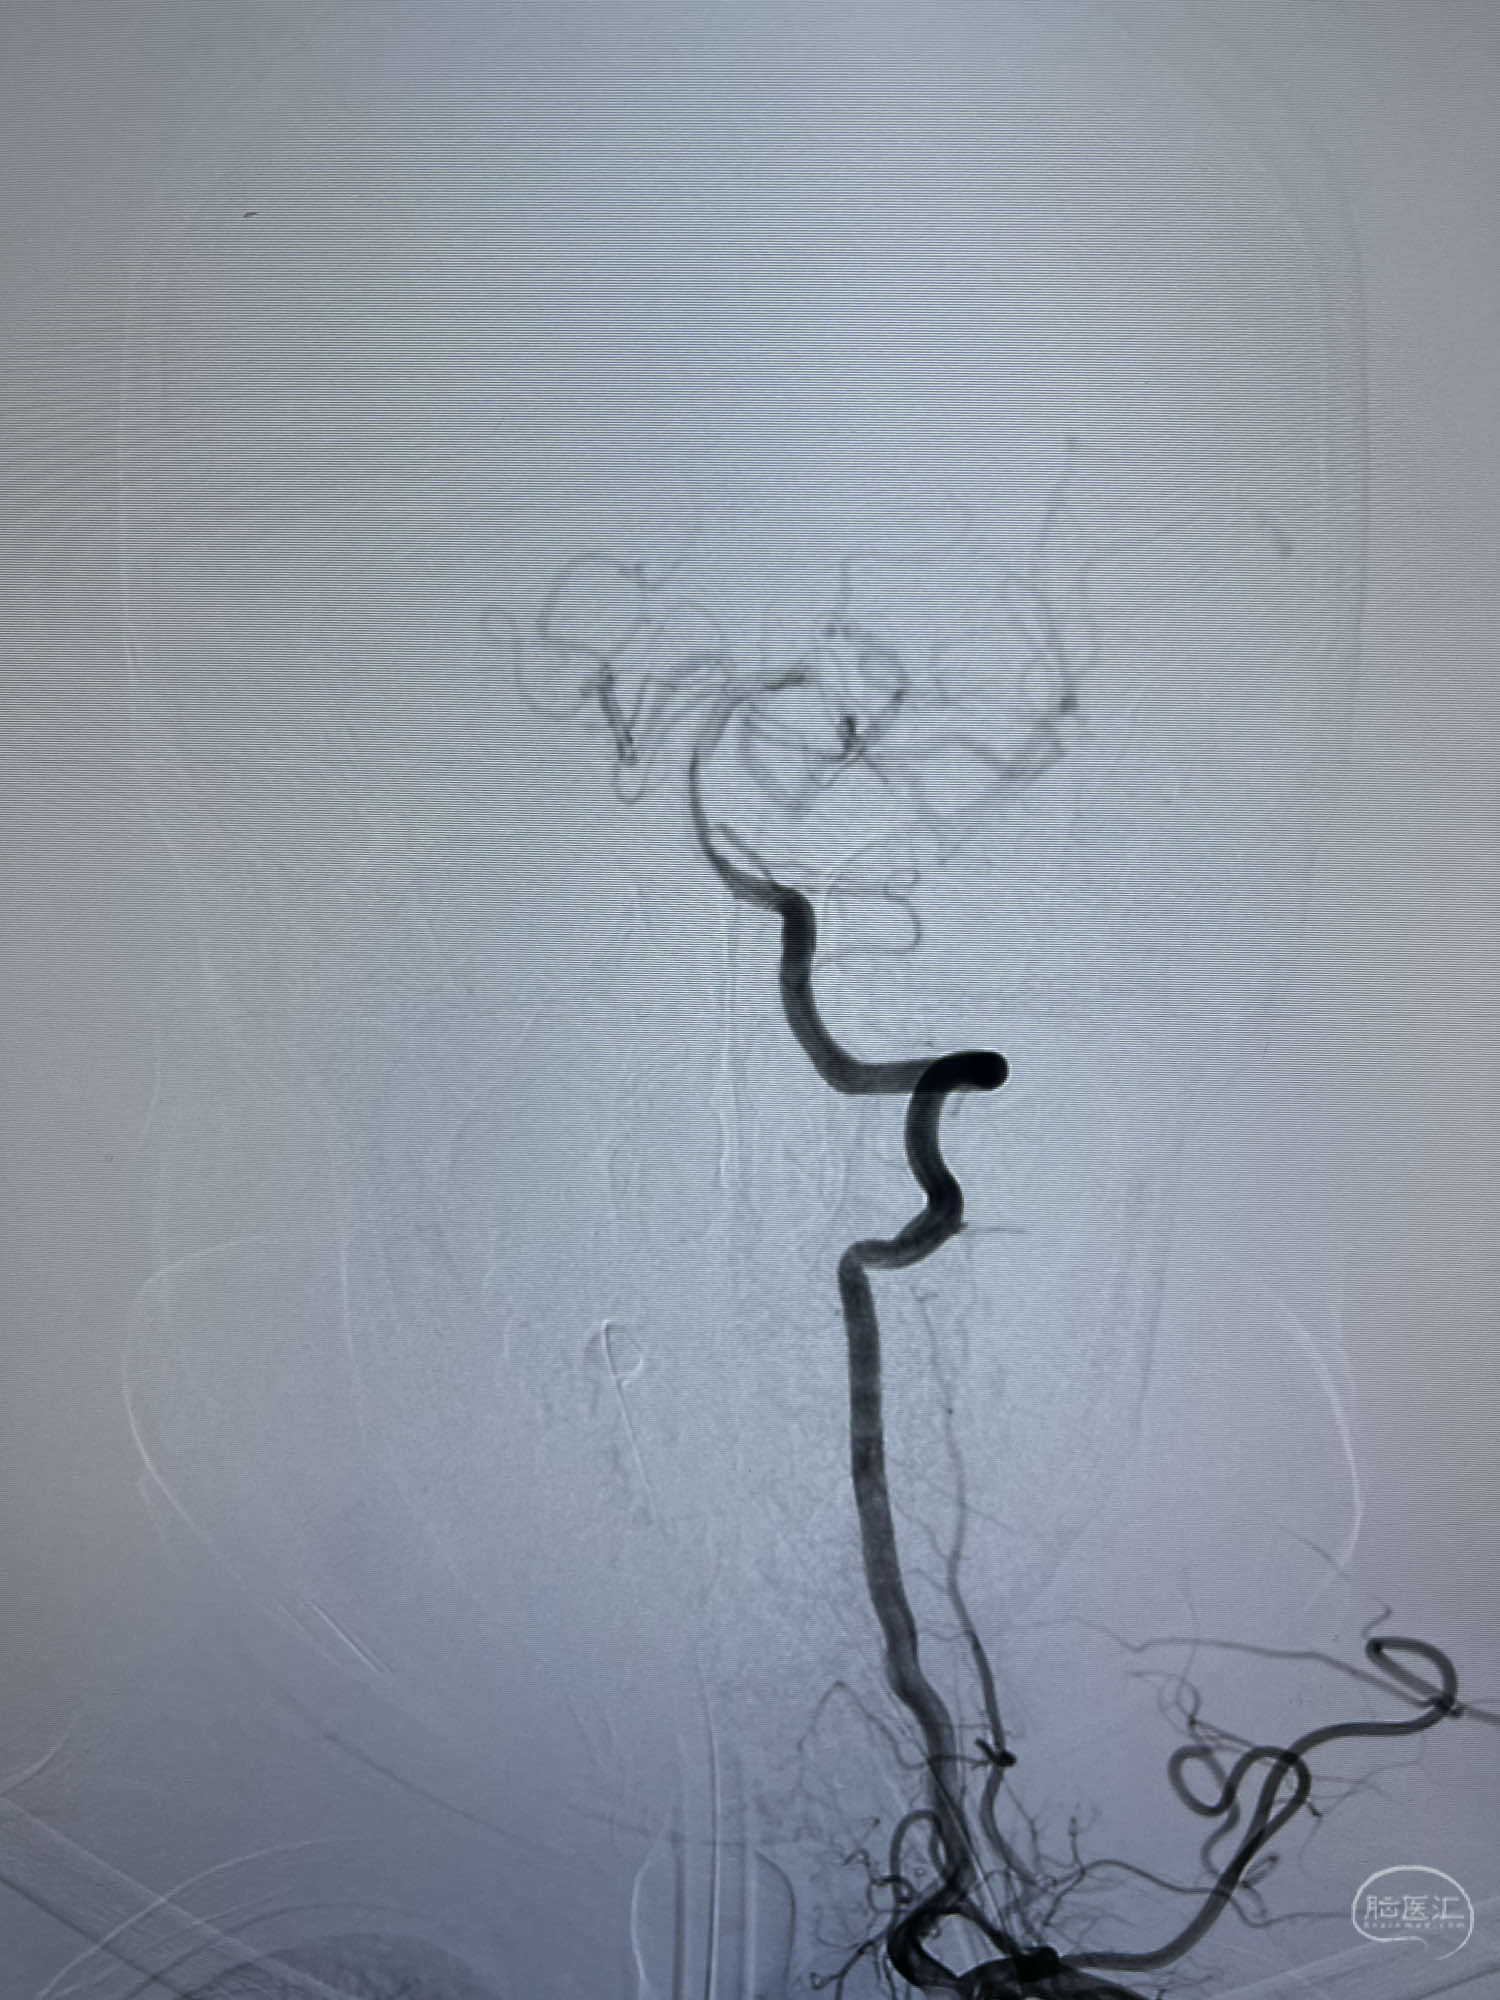

DSA示:左侧颈内动脉眼动脉段以远闭塞,后交通动脉开放,椎基底动脉通过后交通动脉代偿左侧大脑中动脉区域,右侧发出双侧大脑前动脉,右侧大脑中动脉M1末端宽颈动脉瘤,大小约4.3mmx4.6mm。

6F Neuromax➕6F115cm 心玮中间导管建立路径,sychro14微导丝➕VIA21超选至动脉瘤体内近中部,WEB5mmx3mm植入动脉瘤。

WEB瘤内扰流装置5mmx3mm经过“种子、萌芽、开花”三个阶段,打开后良好贴壁,动脉瘤内血液滞留,载瘤动脉通畅。WEB一步到位,通过瘤内扰流的方式起到栓塞动脉瘤的作用,避免了应用支架保护分支血管,简化了操作步骤,降低了术中血栓及出血的风险。